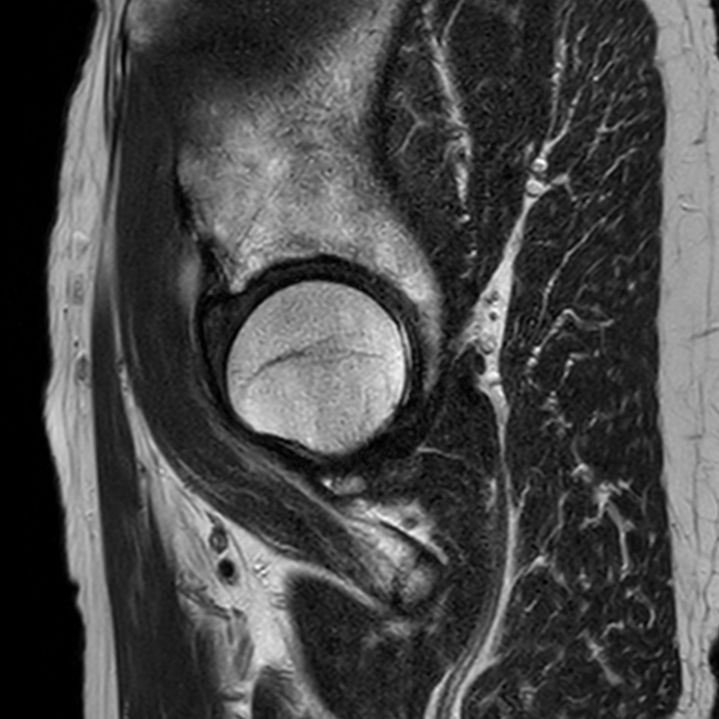

Coronal T1w TSE

Coronal T1w TSESmartSpeed

Coronal T1w TSESmartSpeed Resolution